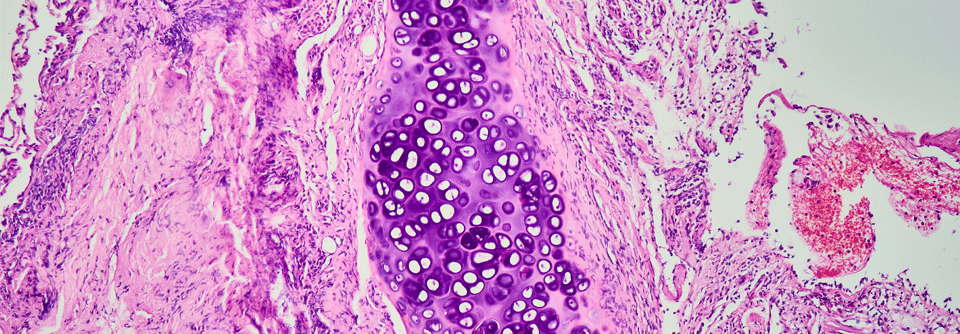

Organisierende Pneumonie

Lungenentzündung, aber kein Erreger

Die Diagnose der organisierenden Pneumonie ist kniffelig, doch der Aufwand lohnt sich. Viele Patienten sprechen gut auf Glukokortikoide an und die…